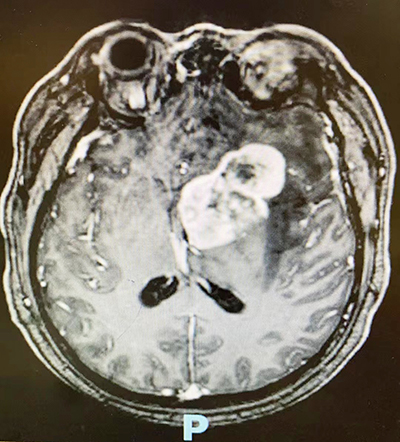

39歲的劉先生因“頭暈、頭痛20余天,加重7天”來到柳州市人民醫院神經外科就診。頭顱CT、MRI檢查提示“顱內占位性病變”。考慮患者病變位于腦深部,手術切除癱瘓可能性極大,且考慮病變為“淋巴瘤”,首選治療方案為化療。如何治療劉先生,幫助其重返工作和生活,成為了神經外科醫生們心中最牽掛的事。

術前CT影像

經過完善的術前準備,手術當天,在麻醉科的配合下,神經外科團隊利用手術機器人導航定位系統,精確定位腫瘤位置,確定手術最佳路徑、手術范圍等,并使用機器人行腫瘤穿刺定位。術中切片提示為“淋巴瘤”,出血僅10ml。